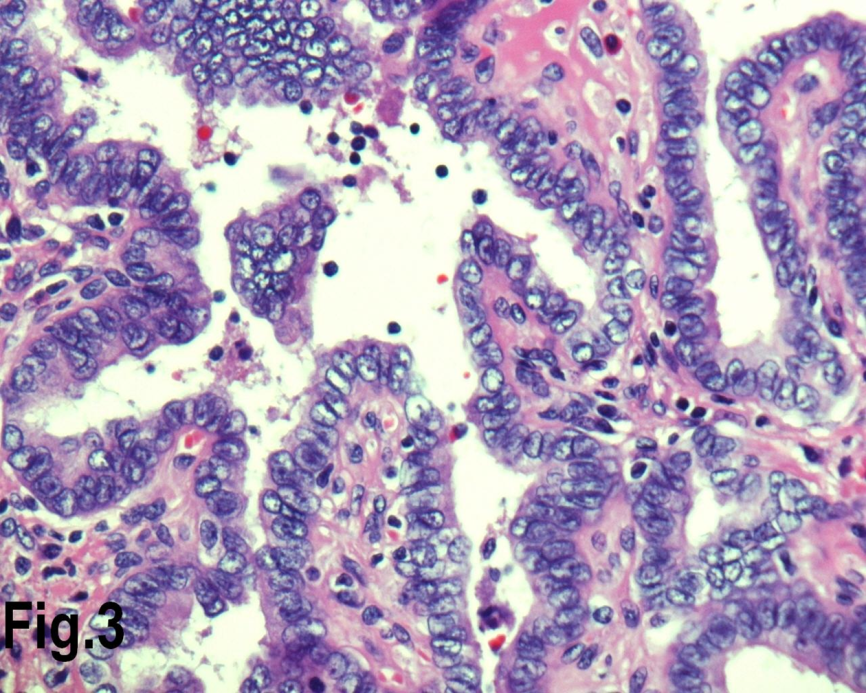

Solitary benign adenomas were found in 23 cases, the peak frequency was fourth and fifth decade. Female accounted for 12 cases (70.5%) for follicular adenoma (Figure 2) and 3 cases (50%) for Hurthle cell adenoma. Thyroid malignancy and it was reported in 62 cases. Papillary carcinoma (Figure 3) was the most common type of thyroid malignancy found in 44 cases (71%) followed by follicular carcinoma (9.6%) (Figure 4), medullary carcinoma (1.6) and poorly differentiated carcinoma (1.6%) (Table 3). The peak incidence for patients with thyroid malignancy in this series was third decade and male to female ratio was 3.7:1.

Figure 3.High power view showing follicles lined by cells with nuclear characteristics of papillary carcinoma, with prominent intra nuclear inclusions (Hematoxylin & eosin, original magnification ×400).